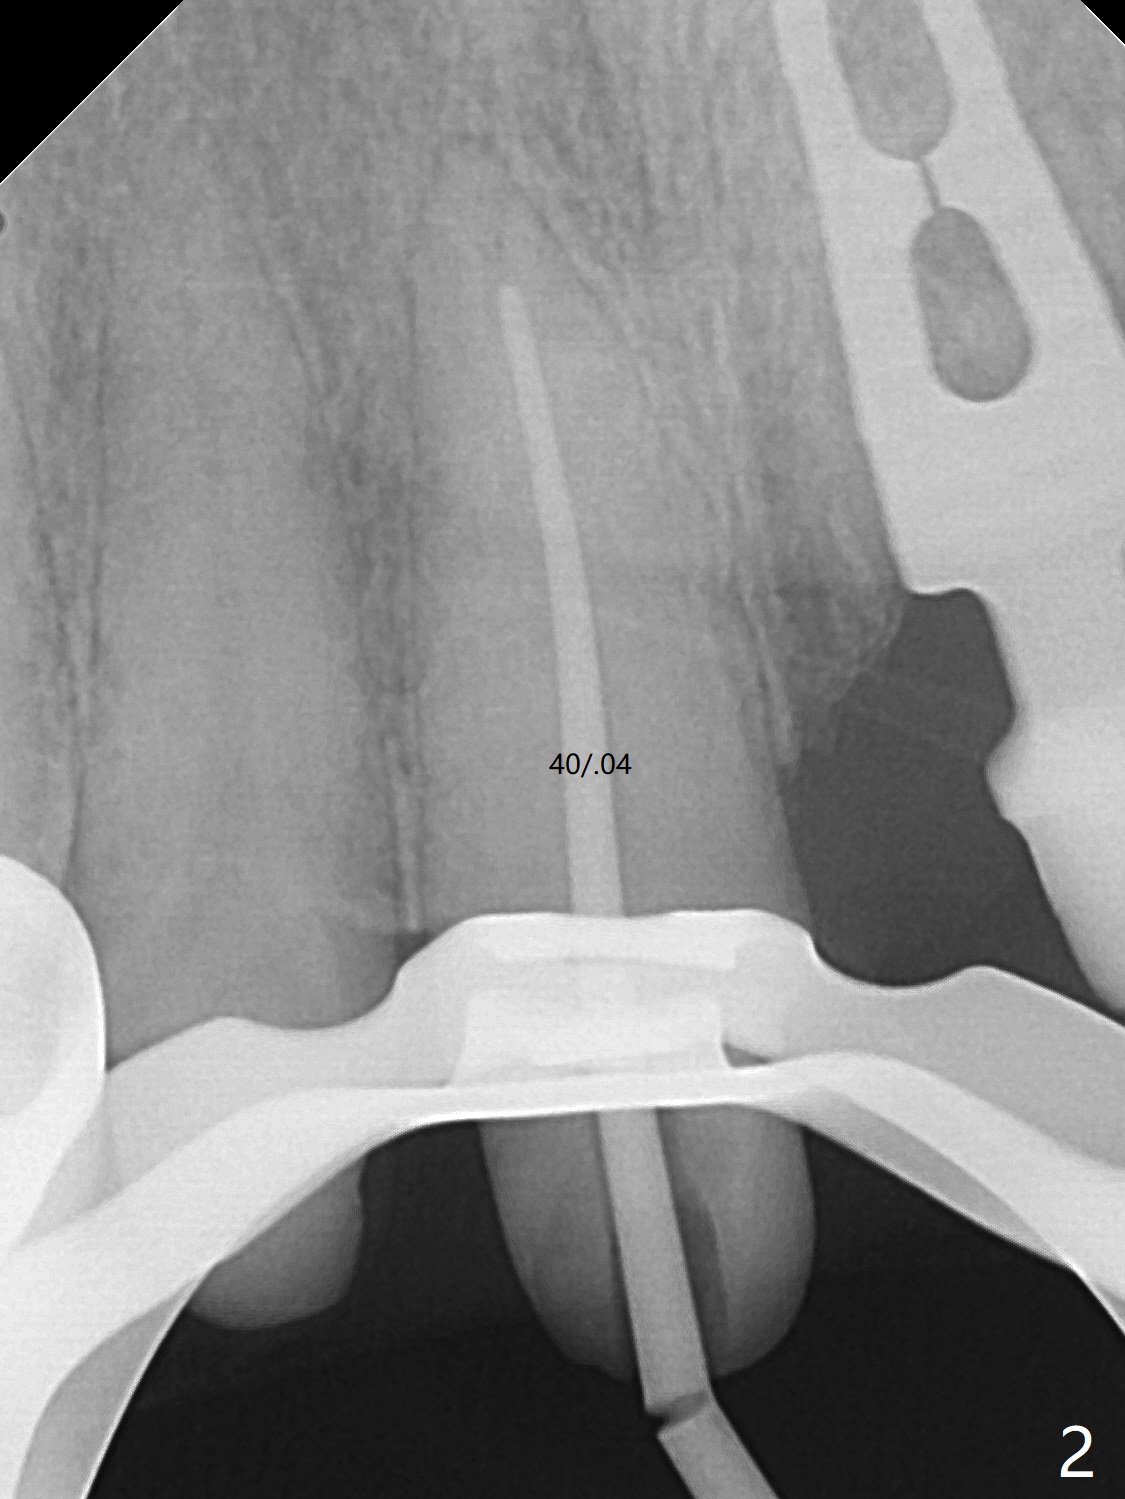

58岁女前牙桥撤除后三个月右上1(8号牙)出现牙髓炎,利用三个月前拍摄CT测定工作长度21.5毫米(图一),与术中根尖测定仪一致,但是40/.04 master cone没有达到工作长度(图二),再次使用根尖测定仪,工作长度22毫米,master cone空管临床上好像达到工作长度,但是加上糊剂,master cone临床上仍然不到工作长度,与根尖片一致(图三),三次切除牙胶尖,三次垂直压缩,仍然没有缓解长度问题(图四)。但愿临床上没有问题,此例是活髓。最终牙冠应用临时粘固剂。如果使用细的牙胶尖(考虑年龄因素),例如30/.04,可能简单些。